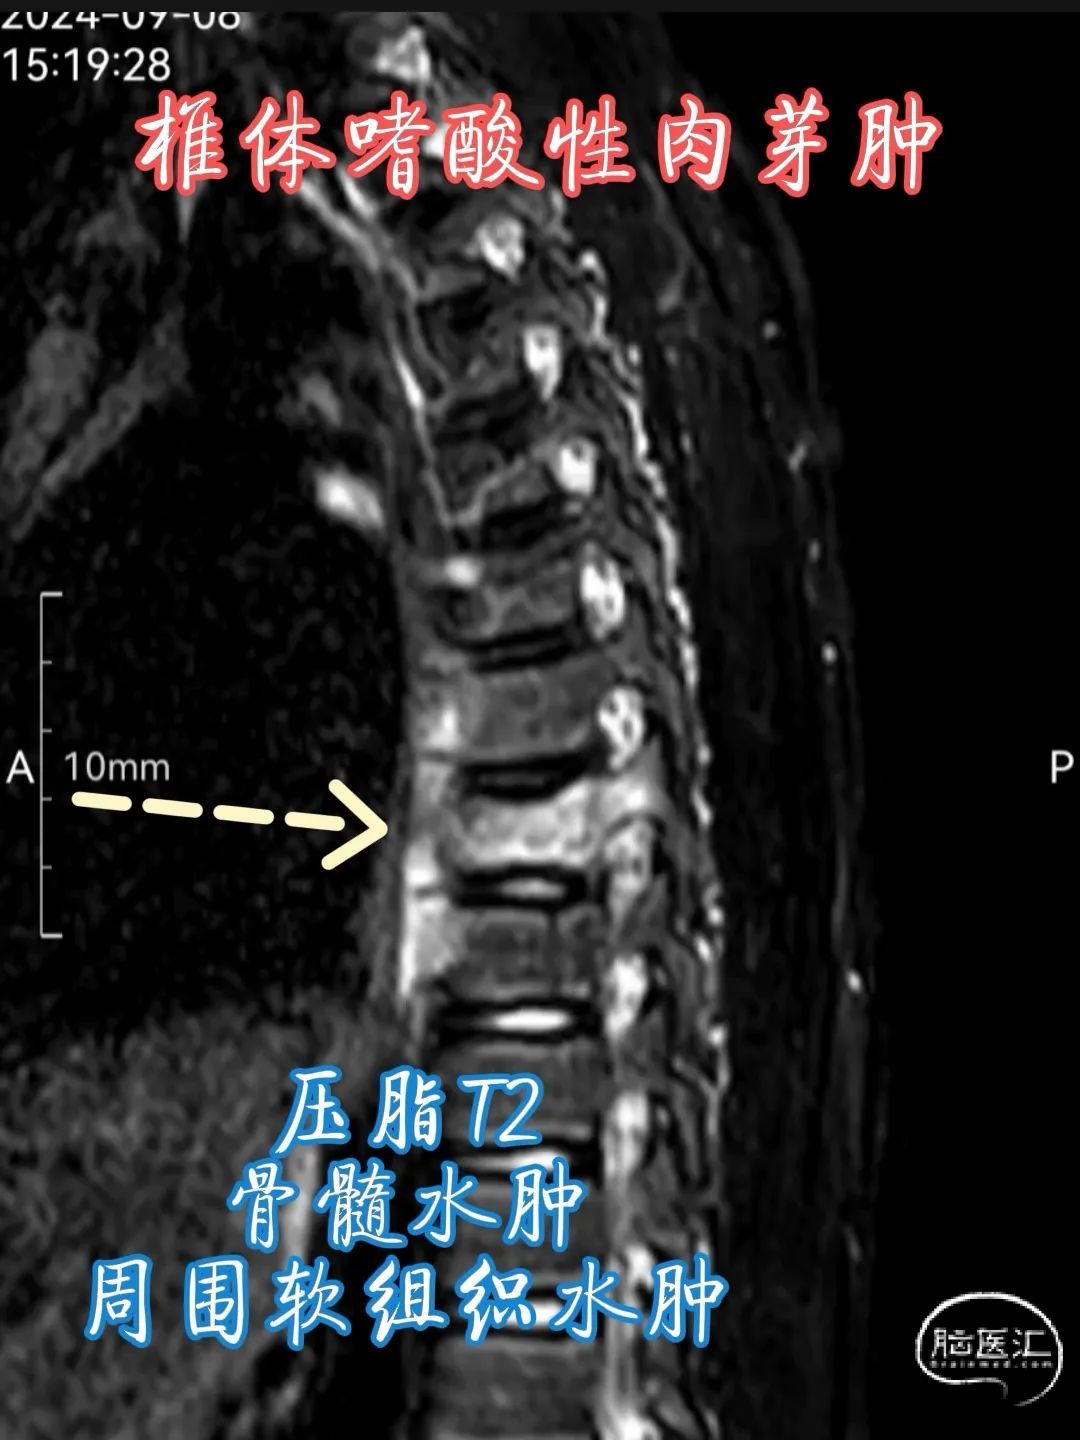

•MRI 检查 :MRI 对于检测椎体嗜酸性肉芽肿具有较高的敏感性,能够清晰地显示病变的范围、部位、形态以及与周围组织的关系。在 T1 加权像上,病变通常呈低到中等信号强度,与正常骨髓相比信号较低;在 T2 加权像上则呈高信号强度,这是由于病变组织内含有较多的水分和黏多糖等成分。此外,MRI 还可显示病变周围的软组织水肿、炎症反应以及神经受压等情况,对于判断病情和制定治疗计划具有重要价值。